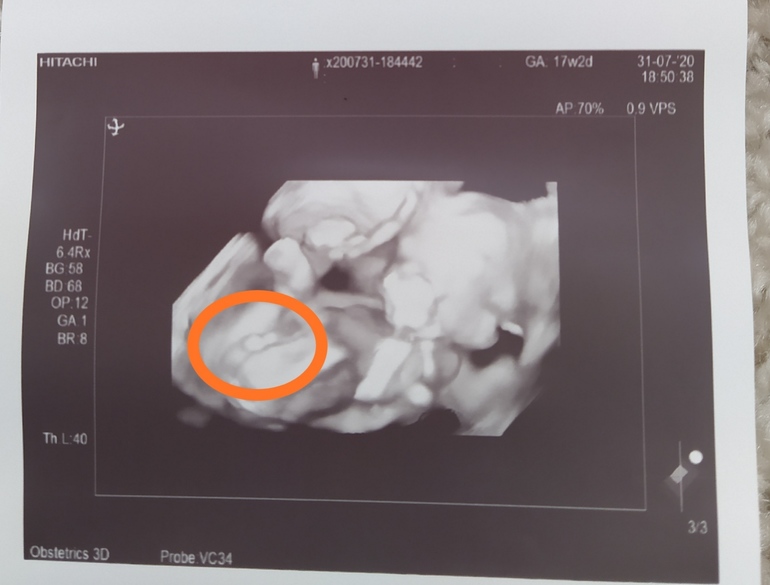

Ну это точно же девочка?

УЗИ, КТГ, доплер18 недель .

Врач 100 % не даёт ,даже 90 %😂

Вот на первой фотке вижу пирожок,а на второй бугорок 🤷♀️ Это обе фотки между ножек.

Оля (я скоро мамой стану снова), Девочка под вопросом. Ноги сильно сжаты, поэтому точно не поставила девочку 🤷♀️

Это 100% девочка. Было подобное фото второе как у вас на вашем же сроке. Врач неопытная тоже озадачилась. Но это девочка